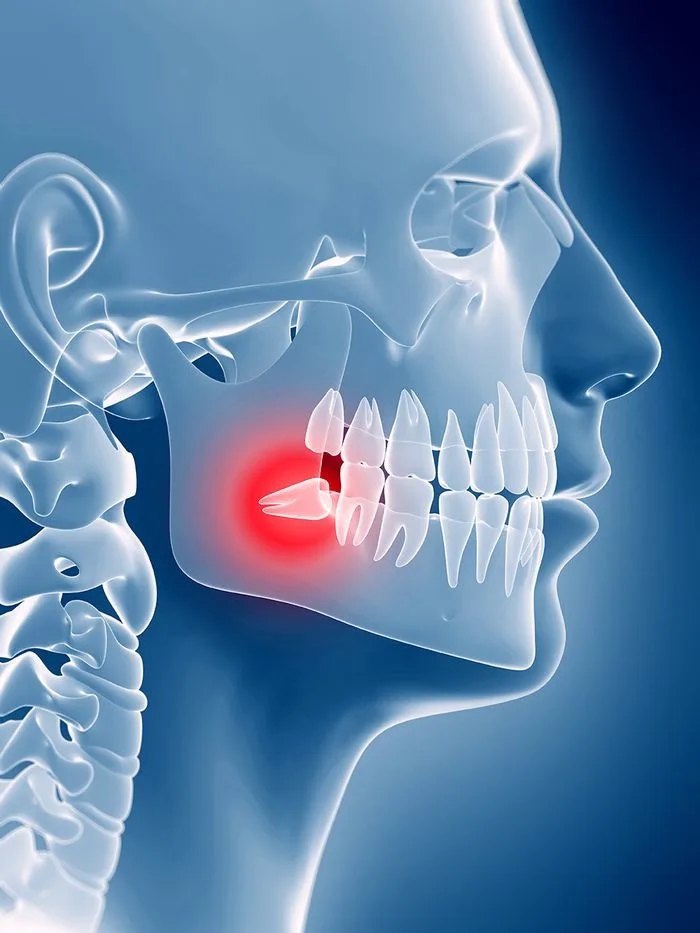

Sometimes a tooth causes more harm than good. While our top priority is to protect your natural teeth, certain issues like infection, impaction, or decay can threaten your overall oral health.Whether you're dealing with painful wisdom teeth or preparing for a dental implant, extractions can be a safe, effective solution to get you out of pain and back to your life. With local anesthesia and gentle care, the procedure is quick, and we’re here to keep you comfortable every step of the way.

Wisdom teeth are often extracted if they’re impacted, causing pain, or crowding surrounding teeth. Your dentist will always explore all options before recommending removal, but sometimes extraction is the best way to protect your long-term oral health.

Delaying a necessary extraction can lead to more serious complications. Infected or decayed teeth can spread bacteria to surrounding teeth, the jawbone, or even into the bloodstream in severe cases. Impacted teeth can cause cysts, damage adjacent teeth, and lead to chronic pain. If your dentist has recommended an extraction, it’s likely to prevent more serious problems down the road.